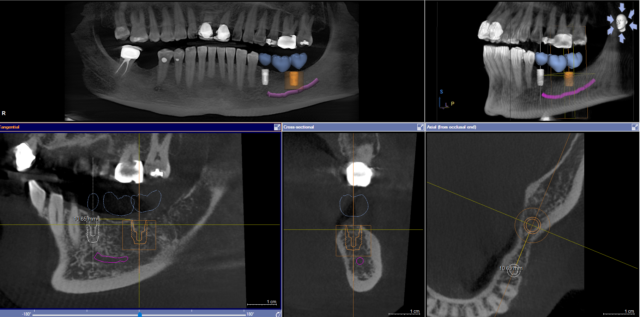

Sure! Here is a picture of where I am so far

I am planning an implant bridge case, planning to place 2 implants, #18 area and #20 area. Creating a guide for this and was wondering if there is a rule about the ideal distance/space to leave for a future pontic on #19 area. Thank you!